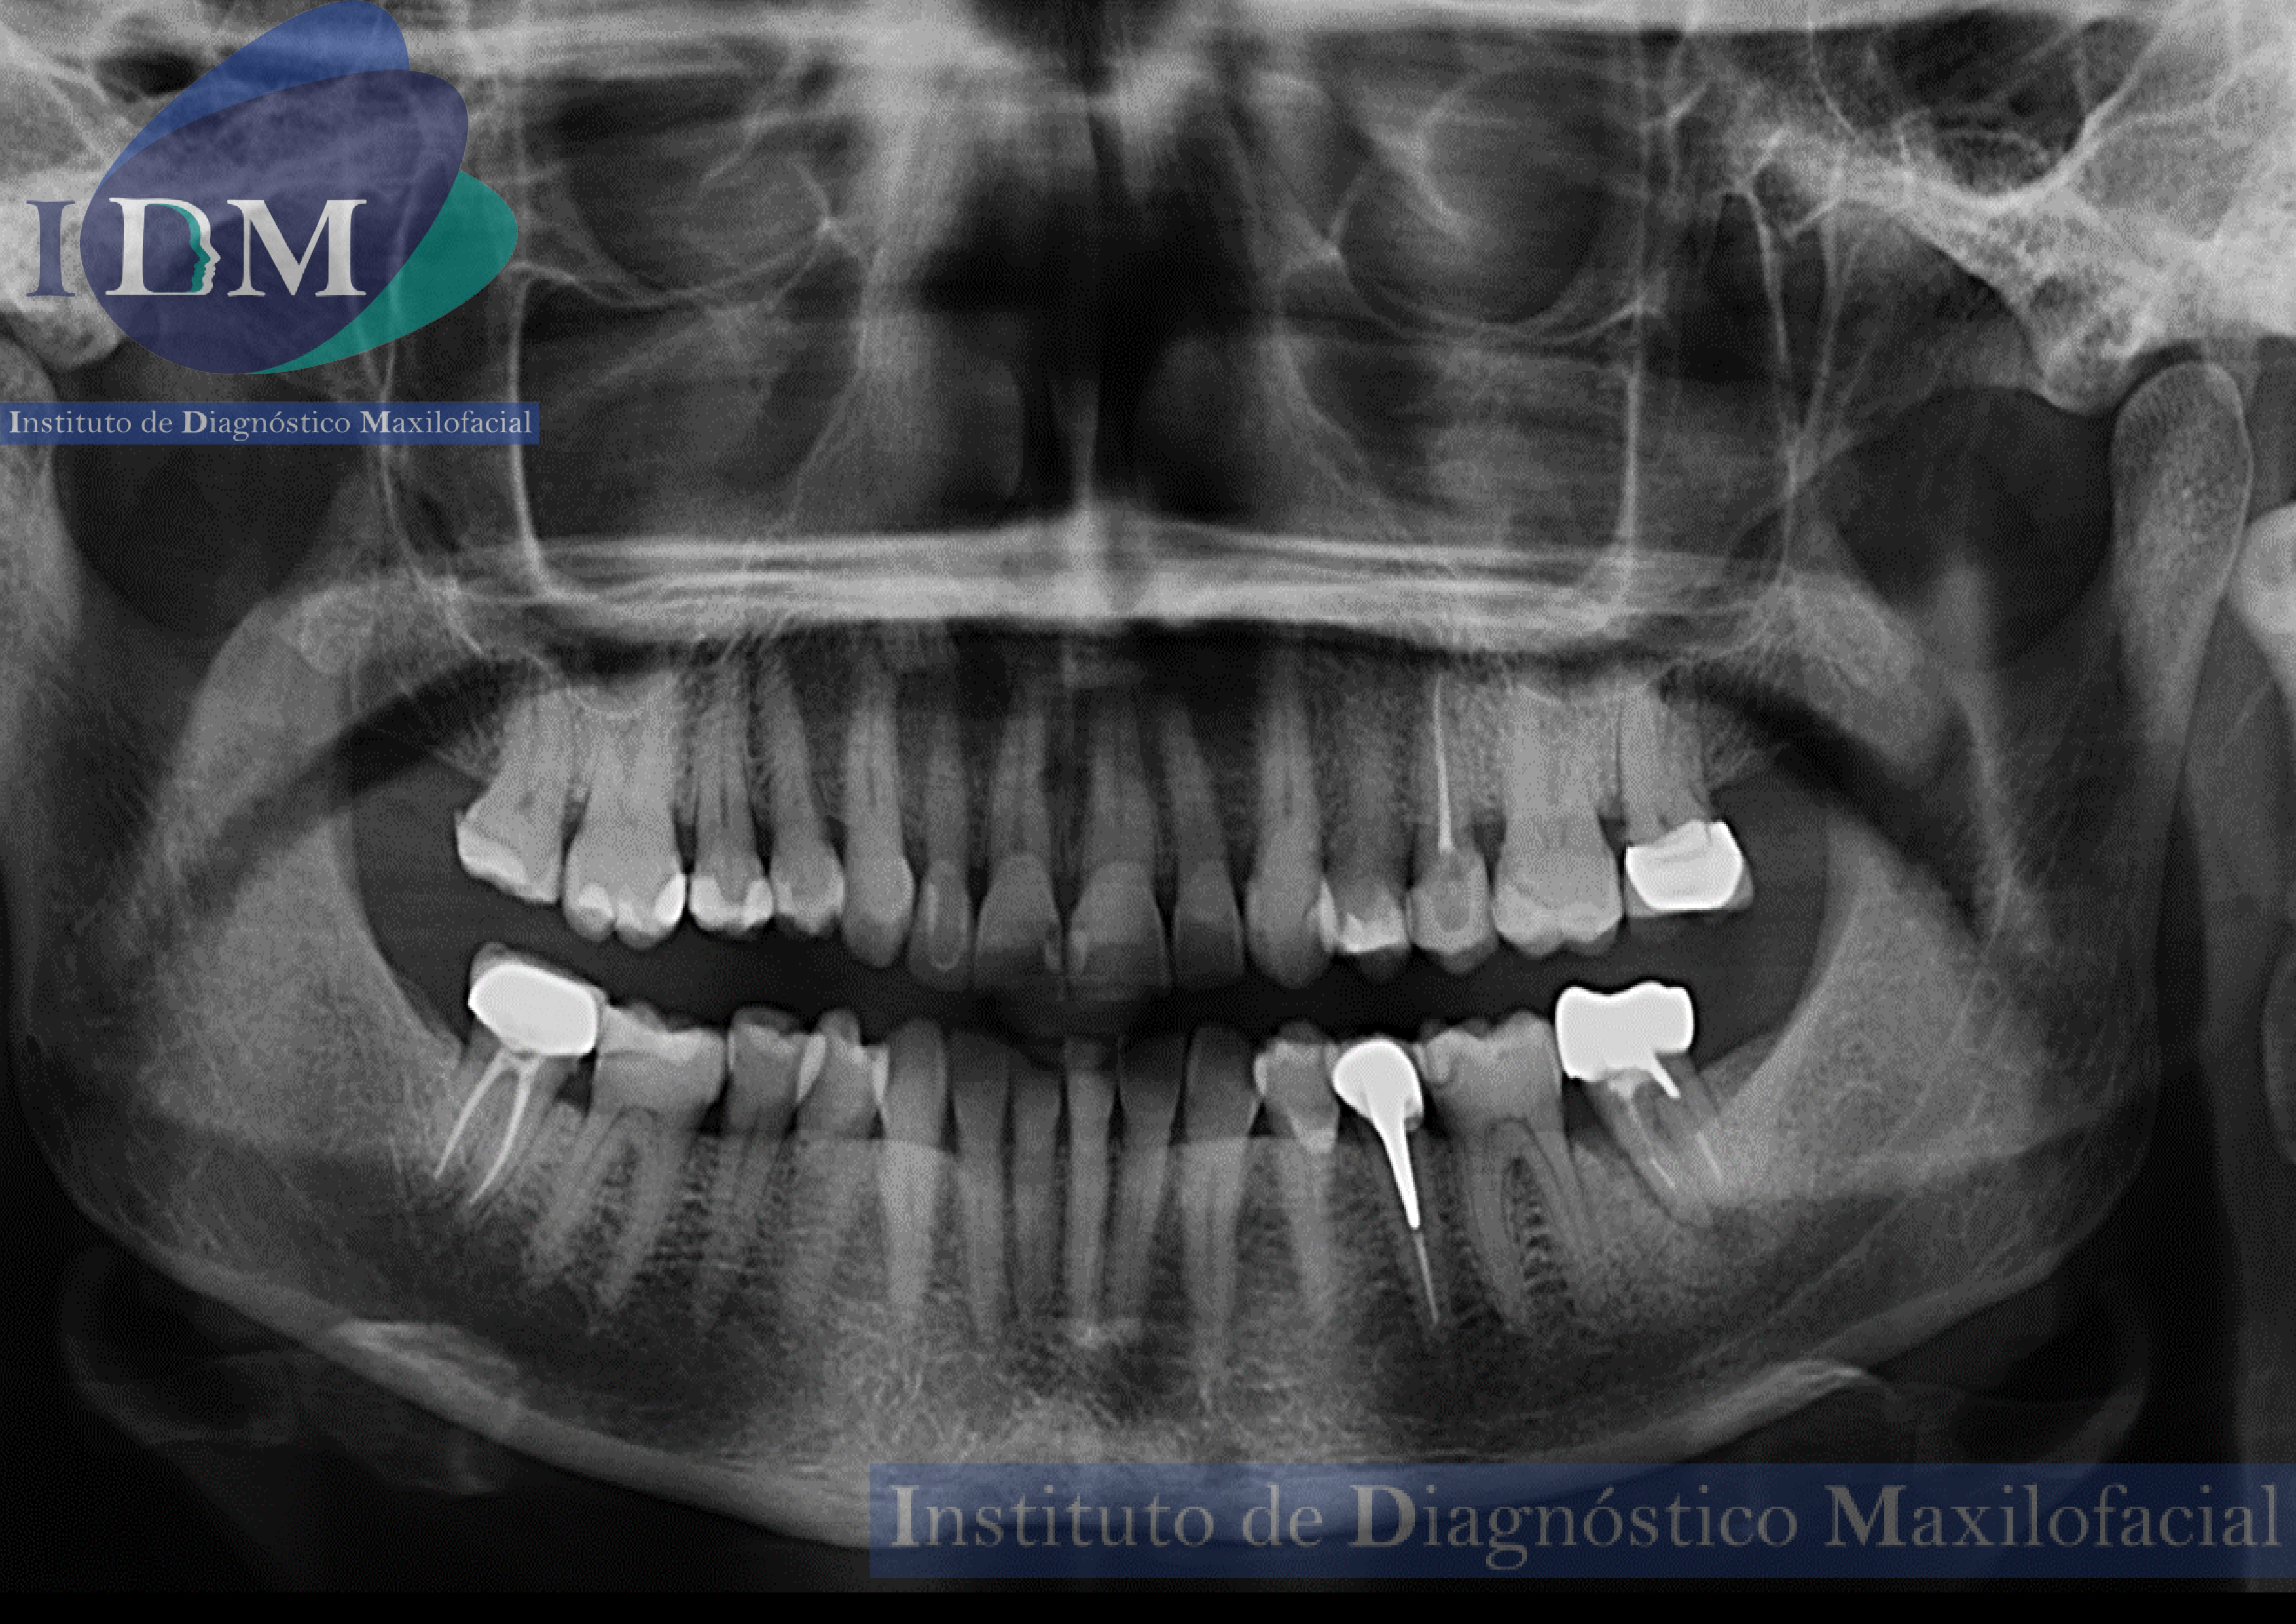

Paciente femenino de 62 años acude al Instituto de Diagnóstico Maxilofacial (sede Miraflores) para evaluación de la pieza 3.7.

Radiografia Panorámica

A la evaluación de la radiografía panorámica se evidencia una neumatización alveolar de senos maxilares, reabsorción ósea alveolar bimaxilar con múltiples piezas con tratamientos restauradores y de obturación de conductos. Siendo lo mas resaltante un proceso osteolítico perirradicular de la pieza 3.7.